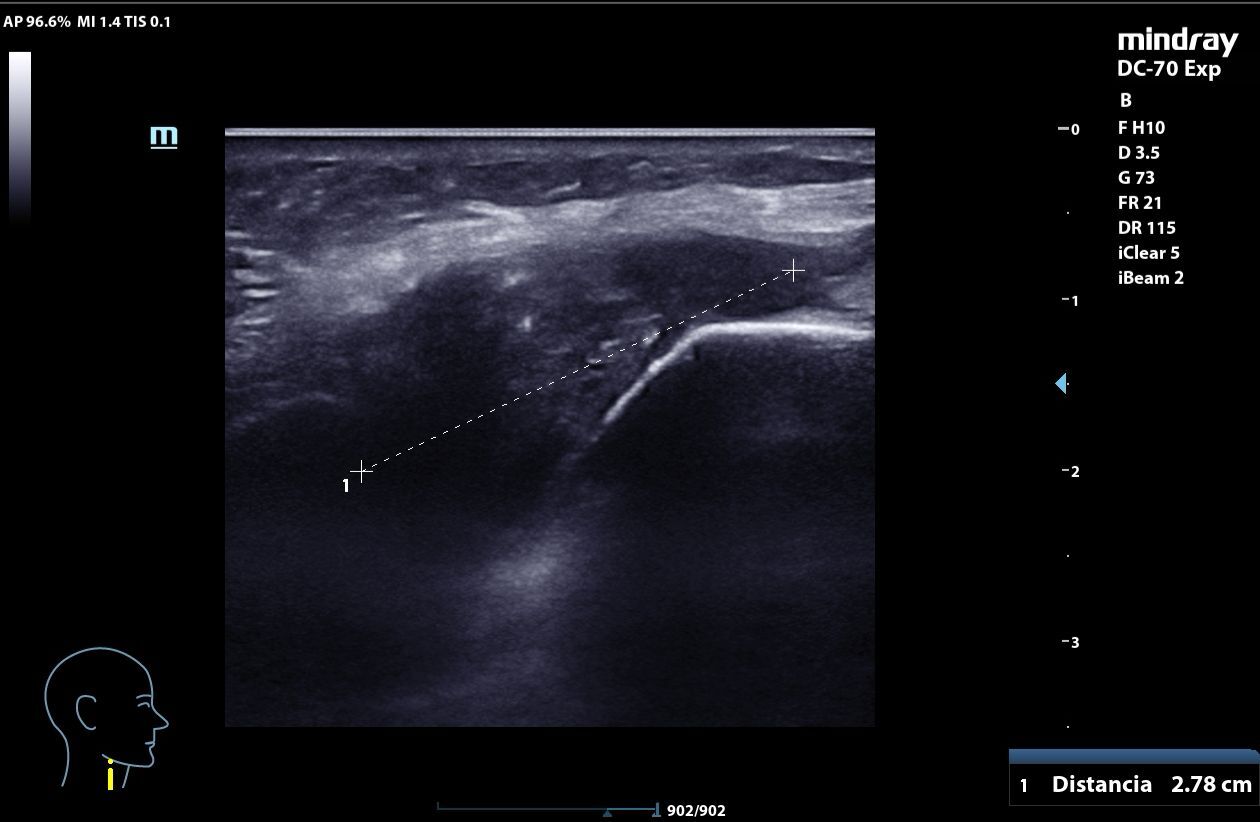

A nivel medial del cuello, por encima del cartílago cricoideo, masa heterogénea, mal delimitada, con calcificaciones internas que generan sombra acústica posterior, elementos hiperecogénicos y algunas zonas anecoicas con refuerzo posterior, con captación en Doppler. La lesión mide 3,06 x 1,48 x 2,78 cm y se mueve con la deglución. En relación con quiste tirogloso complicado o proceso neoformativo.